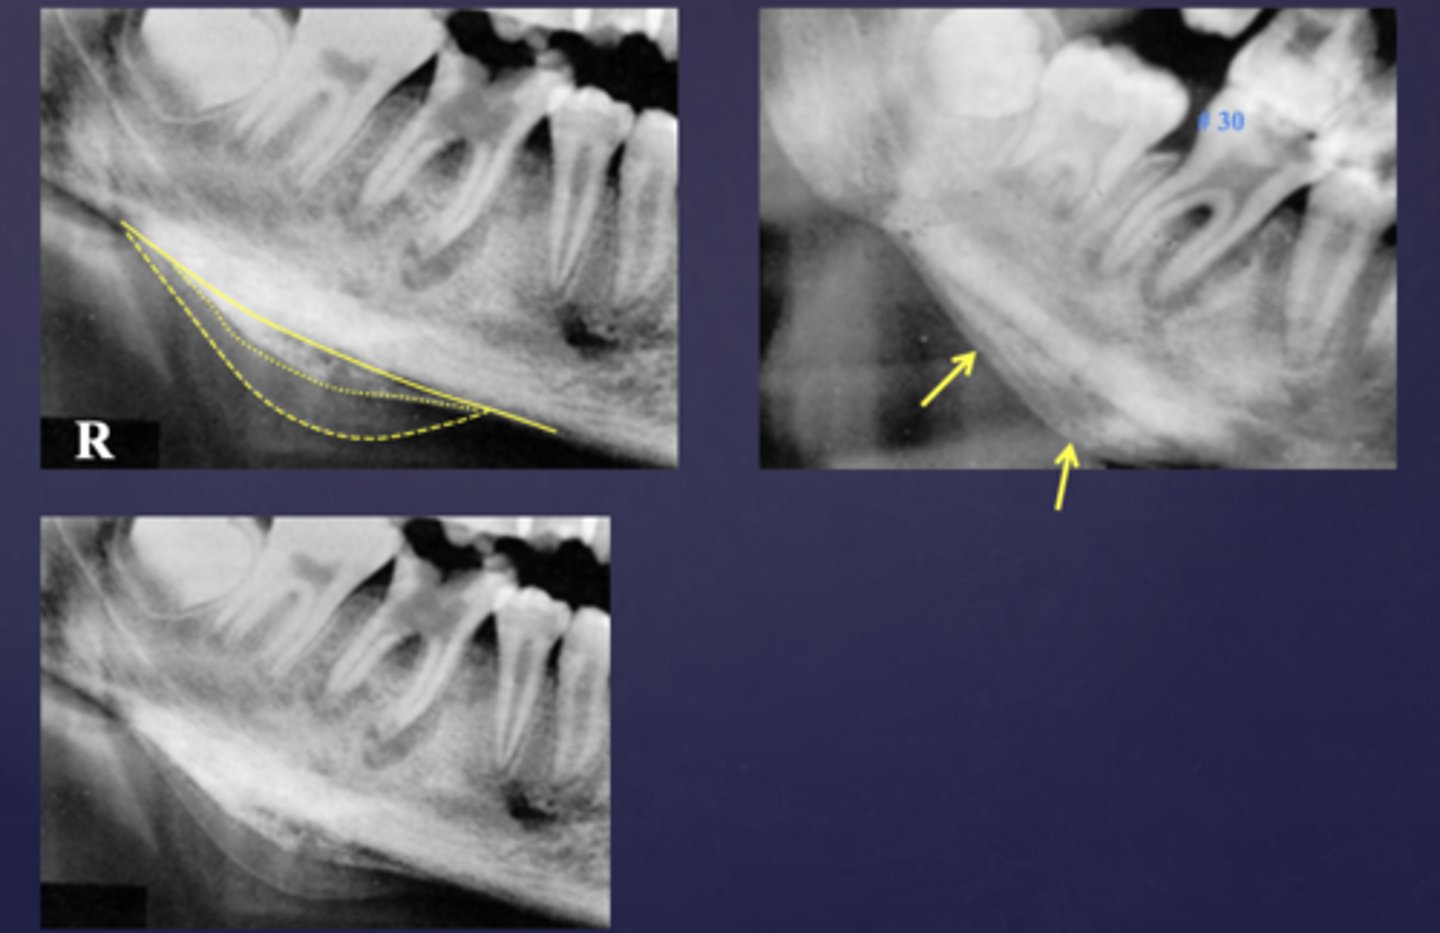

What are two defects that the arrows are pointing to?

- Widened PDL

- Sclerosis

These arrows are pointing at what?

moth-eaten appearance of acute osteomyelitis

The moth eaten appearance is associated with what?

acute osteomyelitis, mixed radiolucent/radiopaque areas

What is the black arrow pointing at?

sequestrae

What is the white arrow pointing at?

periosteal reaction

periosteal reaction (increased bone density)

sequestra